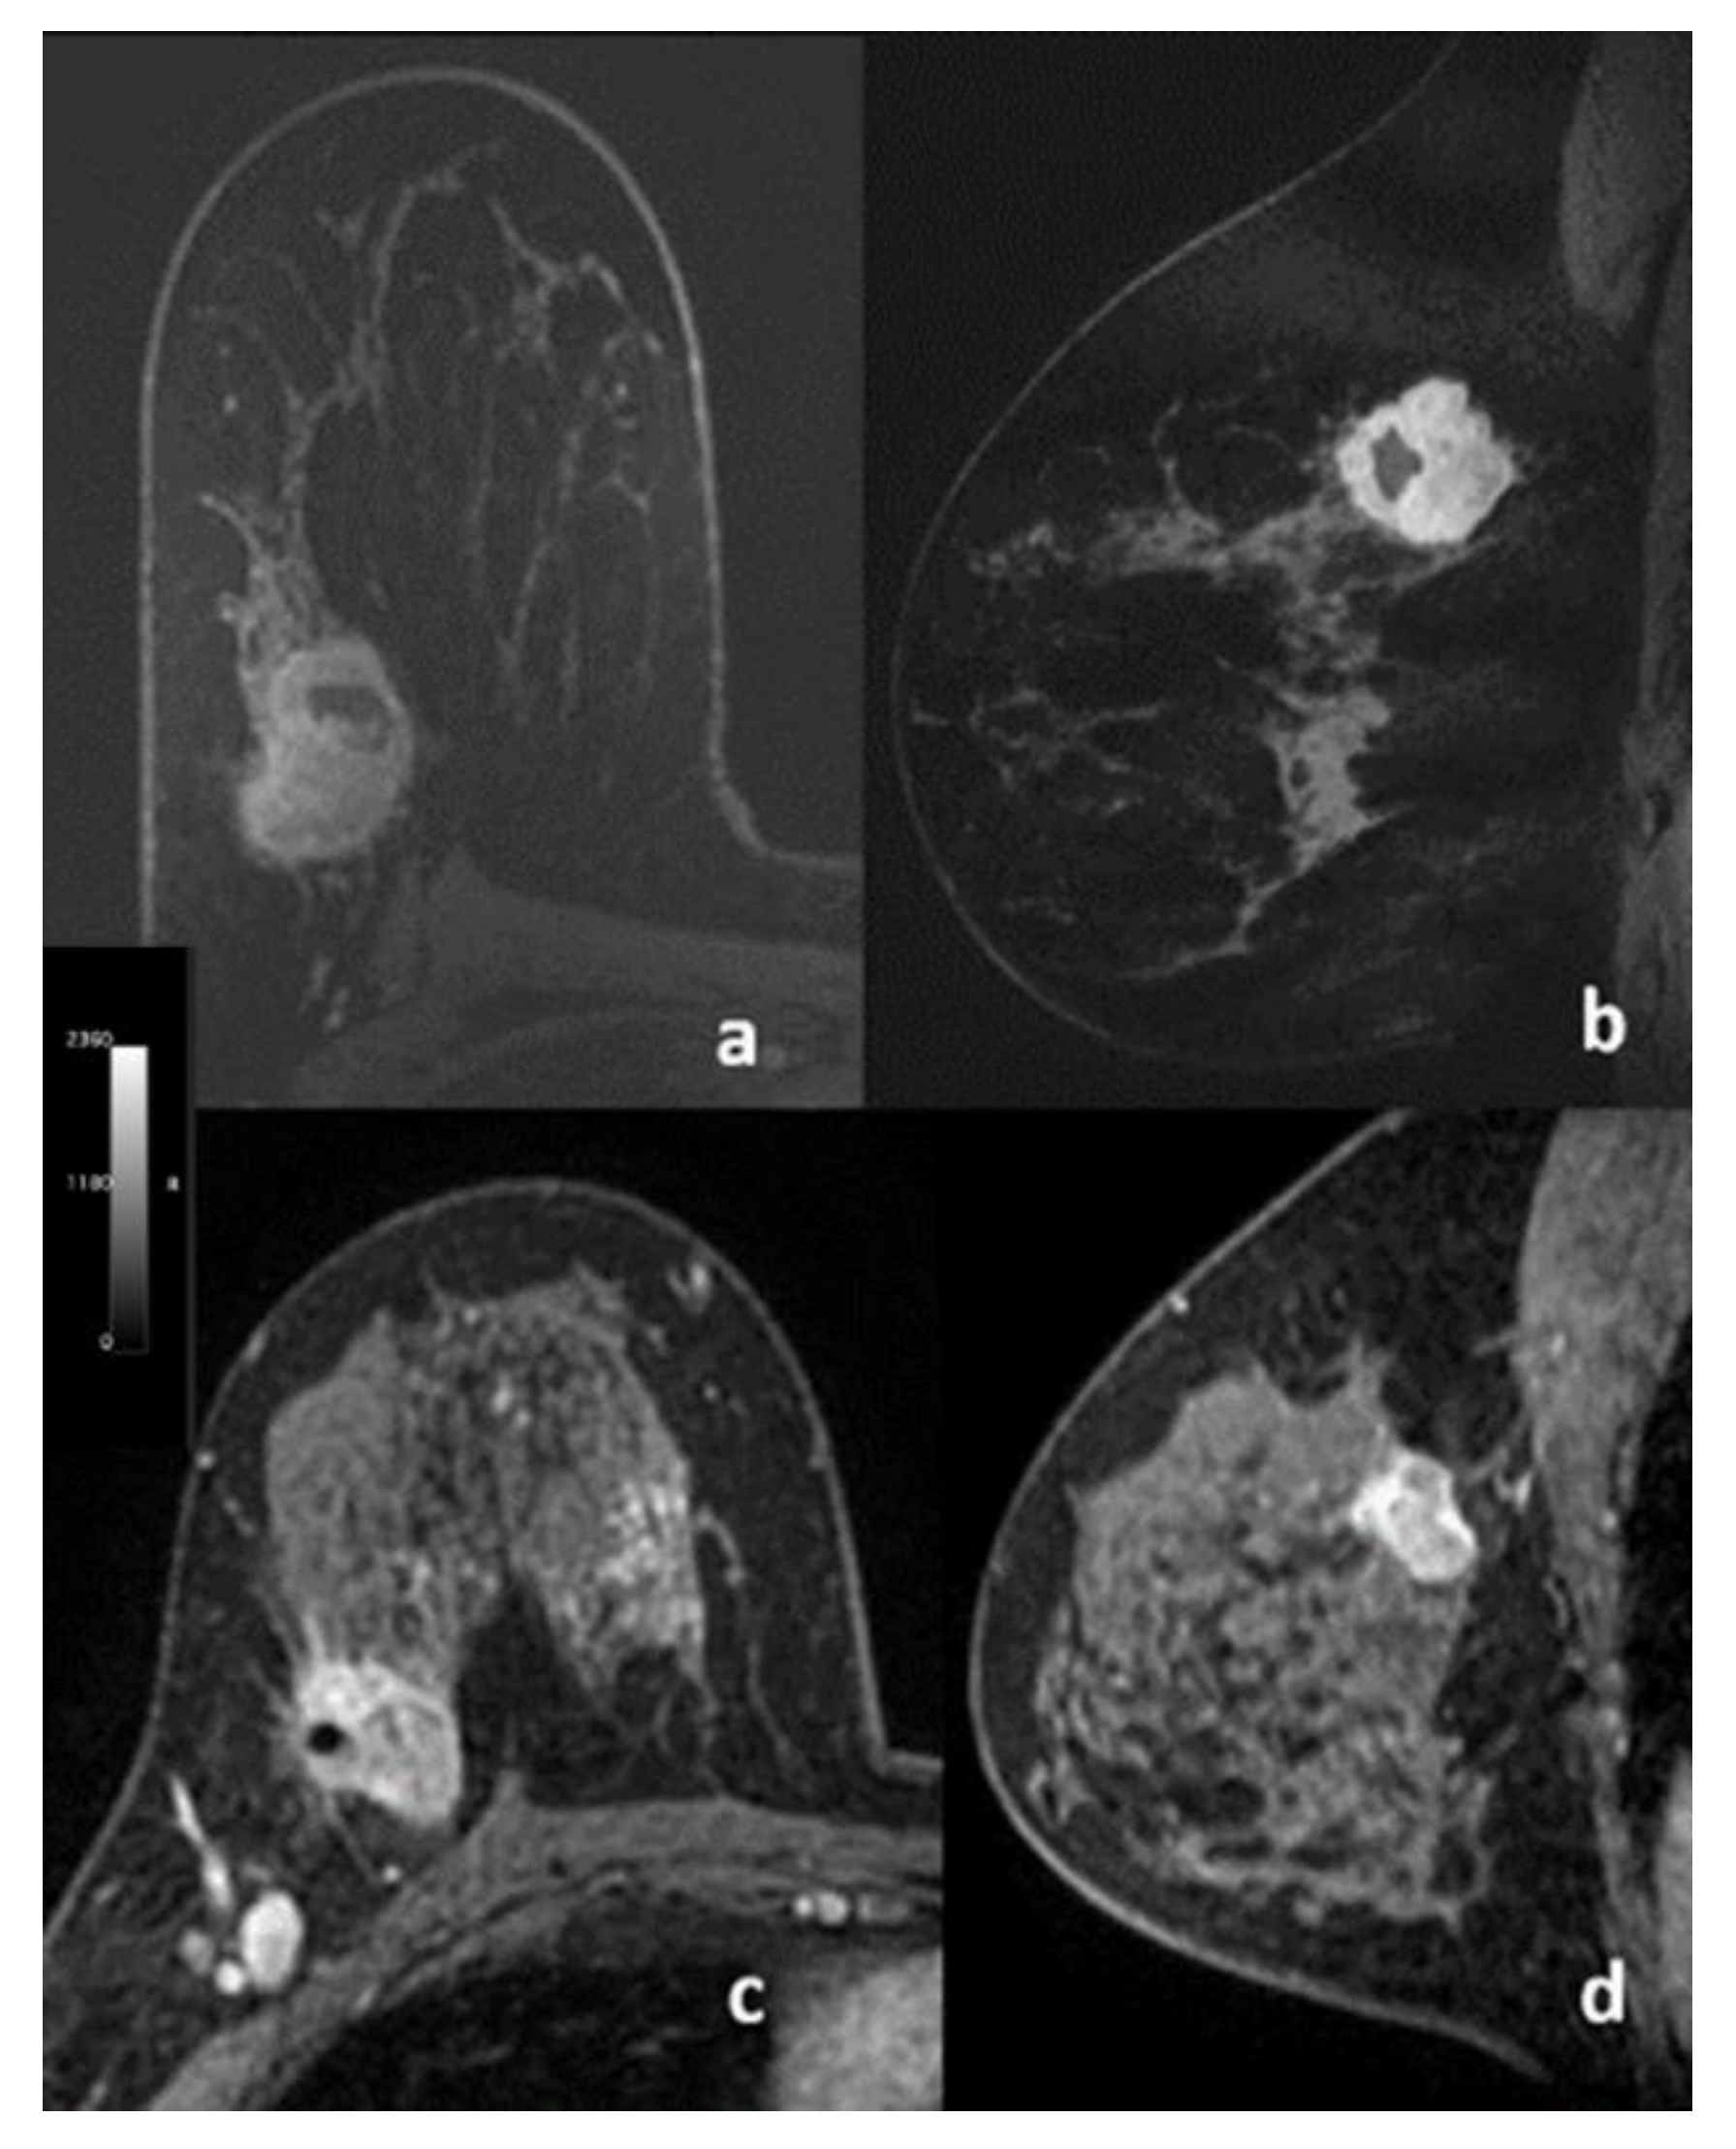

2.3. Qualitative Imaging Assessment

2.5. Radiomics Analysis

3.2. Radiomics Analysis and ML